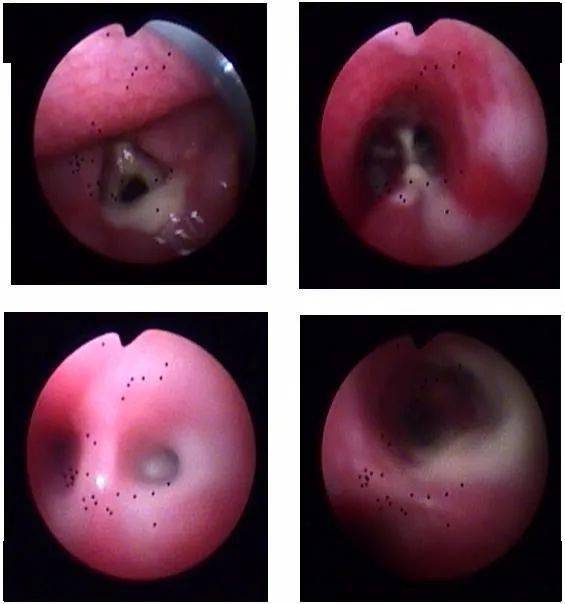

脓痰在气管里的状态,与我们平常见到的不大一样

【讨论】咳嗽,咳黄色脓痰半年,有病理,一周后公布

(气道清理出的大量黄脓痰液)67文:马建岭,董尚